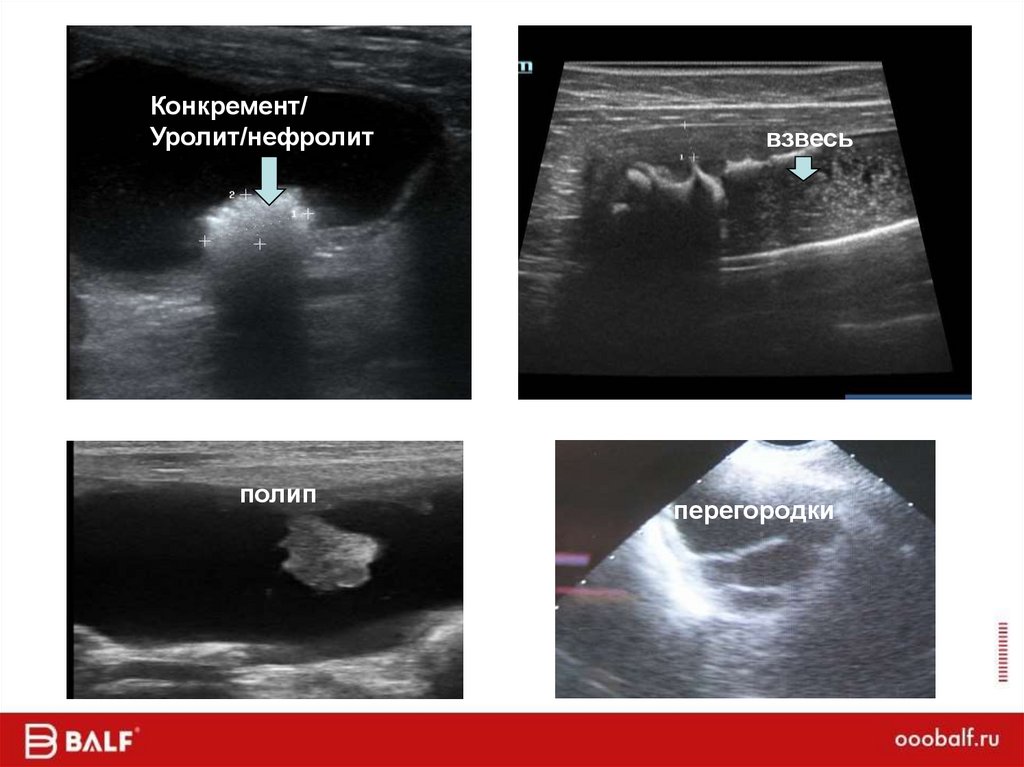

Карта цвета

34.

Конкремент/

Уролит/нефролит

полип

взвесь

перегородки